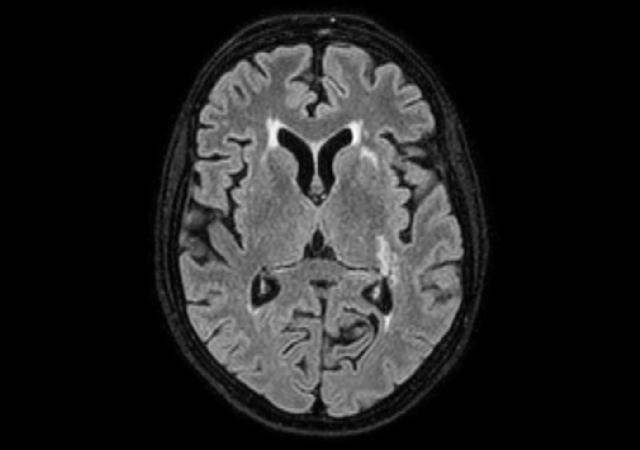

DWI (b1000)